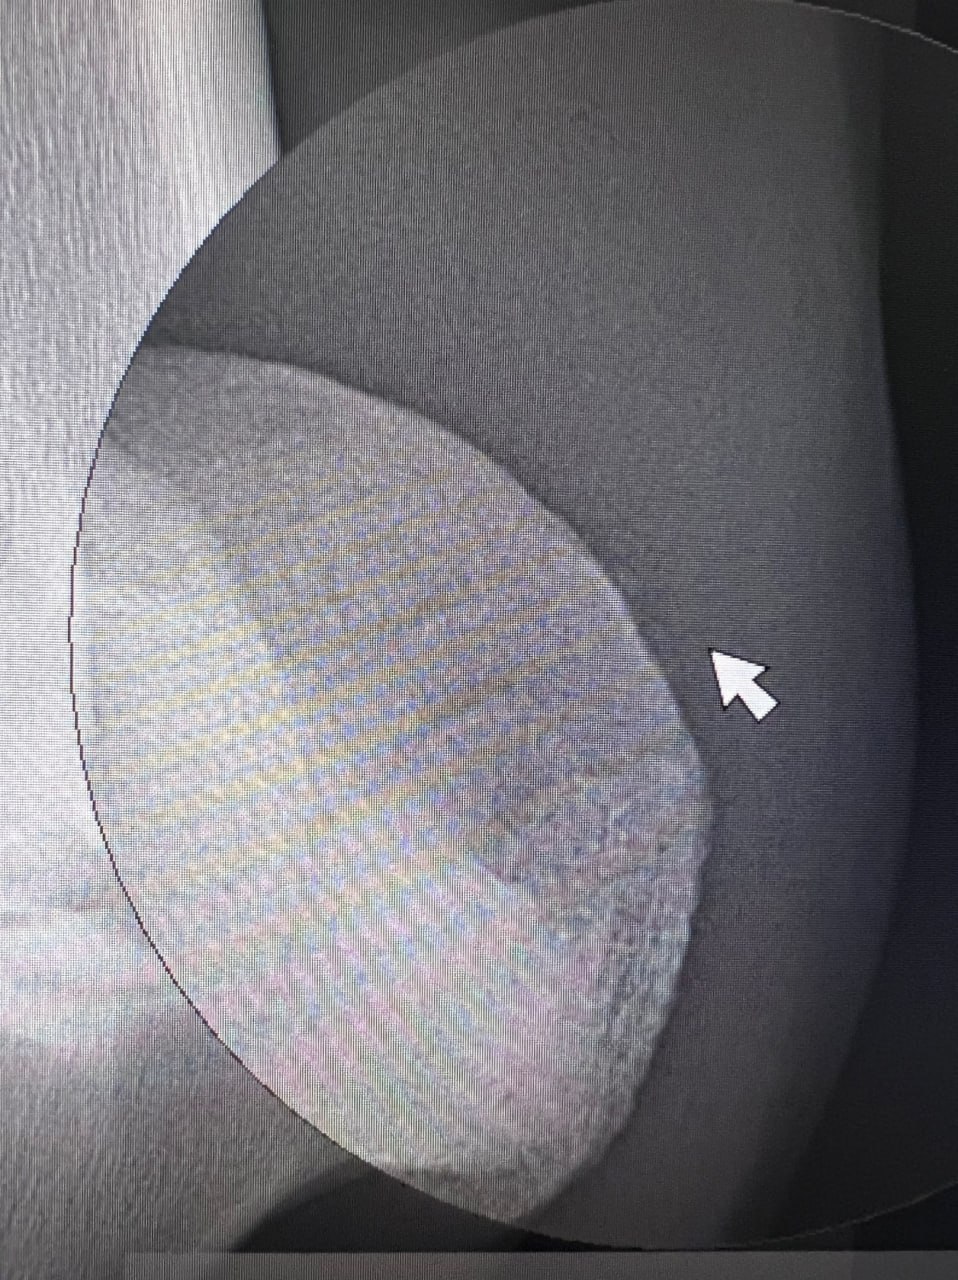

В клинику была делегирована лошадь 12 лет с хронической хромотой более года на правую грудную конечность.

По результатам обследования был получен положительный результат диагностической анестезии дистальных пальмарных пальцевых нервов (над копытом), но на рентгеновских снимках не было отмечено явных изменений, объясняющих эту хромоту.

Результаты МРТ показали, что на поперечном Т2 изображении отмечена нерегулярность субхондральной кости на дорсальной части навикулярной кости в месте образования сустава с промежуточной фалангой (венечной костью), а также нерегулярность пальмарного кортикала промежуточной фаланги. Хроническое разрушение хряща.